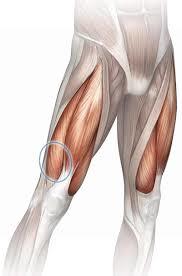

which is this muscle?

innervation?

movement [2]

which is this muscle: sartorius

innervation: femoral nerve

movement [2]: flexes hip AND knee